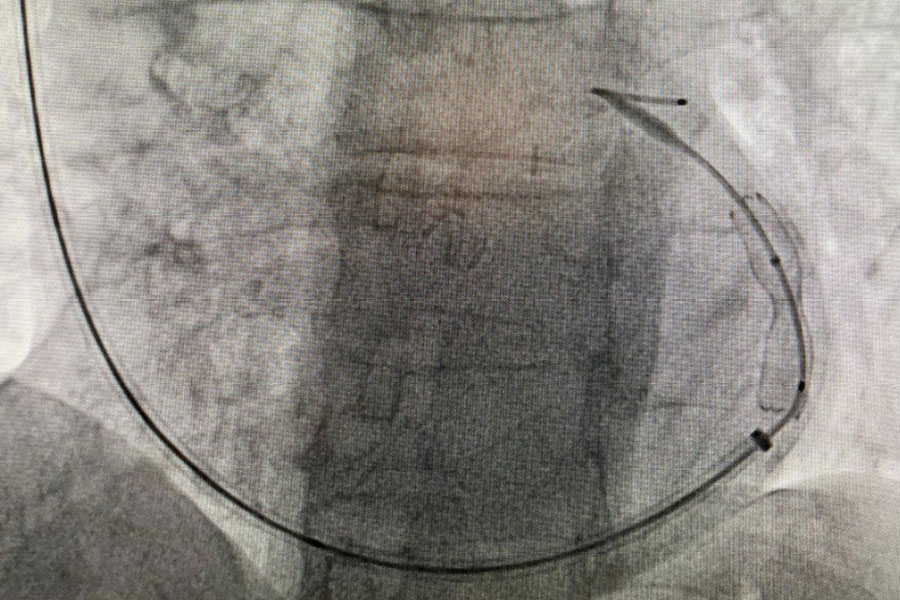

W Klinice Kardiologii UCKWUM przeprowadzono pierwszą w Polsce implantację nowego, samorozprężalnego reduktora przepływu do zatoki wieńcowej A-Flux Vahaticor. Jednocześnie był to pierwszy na świecie zabieg implantacji tego urządzenia u pacjentki z dławicą oporną w przebiegu choroby mikrokrążenia wieńcowego. Urządzenie to pozwala na zwiększenie tzw. całkowitej rezerwy wieńcowej, co stwarza szansę na poprawę jakości życia u chorych z nasiloną dysfunkcją mikrokrążenia, u których uporczywe dolegliwości w klatce piersiowej utrzymują się pomimo optymalizacji farmakoterapii. Reduktor przepływu jest urządzeniem, wszczepianym w znieczuleniu miejscowym, który po implantacji doprowadza do stopniowego przekrwienia uprzednio niedokrwionych obszarów serca. Konstrukcja nowoczesnego urządzenia A-Flux Reducer System pozwala na jego wcześniejsze pokrycie śródbłonkiem, czyli szybsze gojenie się naczynia po implantacji i tym samym wcześniejsze uwolnienie od objawów dławicy.

Kliniką Kardiologii WUM kieruje prof. Marcina Grabowskiego. Zabieg wykonany został 26 lipca przez zespół w składzie: dr hab. Mariusz Tomaniak (operator), prof. Janusz Kochman (operator), dr Francesco Giannini (proktor), Katarzyna Pałyska, Katarzyna Michalska (pielęgniarki), Stanisław Drozdowski (technik).